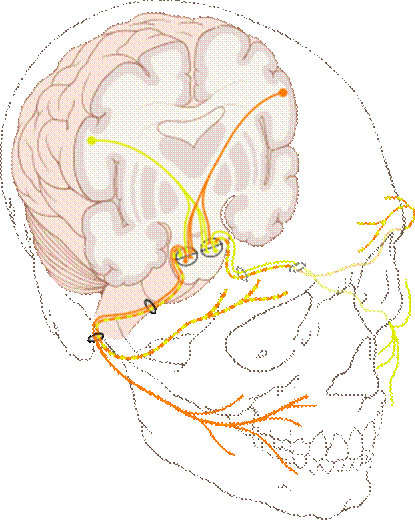

https://upload.wikimedia.org/wikipedia/commons/thumb/1/1f/Cranial_nerve_VII.svg/300px-Cranial_nerve_VII.svg.png

顔面神経

顔面神経(がんめんしんけい、facial nerve)は、12ある脳神経の一つで第七脳神経(CNVII)とも呼ばれる。

狭義の顔面神経は、顔面に分布し主として表情筋の運動を支配する。この神経と内耳神経の間に中間神経と呼ばれる神経があり、広義にはこれを含めて顔面神経と呼ぶ。内耳神経と一緒に側頭骨錐体を貫き、さらに単独で顔面神経管という弓状の骨の管を通り、茎乳突孔から出てきて顔面全体に分岐する。顔面神経管を通る途中から涙腺唾液腺分泌味覚(舌の前部3分の2)などに関係する枝が出て骨の細管を通り抜け関連する神経節舌神経などに入っていく。顔面神経の神経線維には4種類あり、特殊内臓遠心性線維(special visceral efferent fiber, SVE) 一般内臓遠心性線維 (general visceral efferent fiber, GVE) 特殊内臓求心性線維 (special visceral afferent fiber, SVA) 一般体性求心性線維 (general somatic afferent fiber, GSA) と呼ばれる。